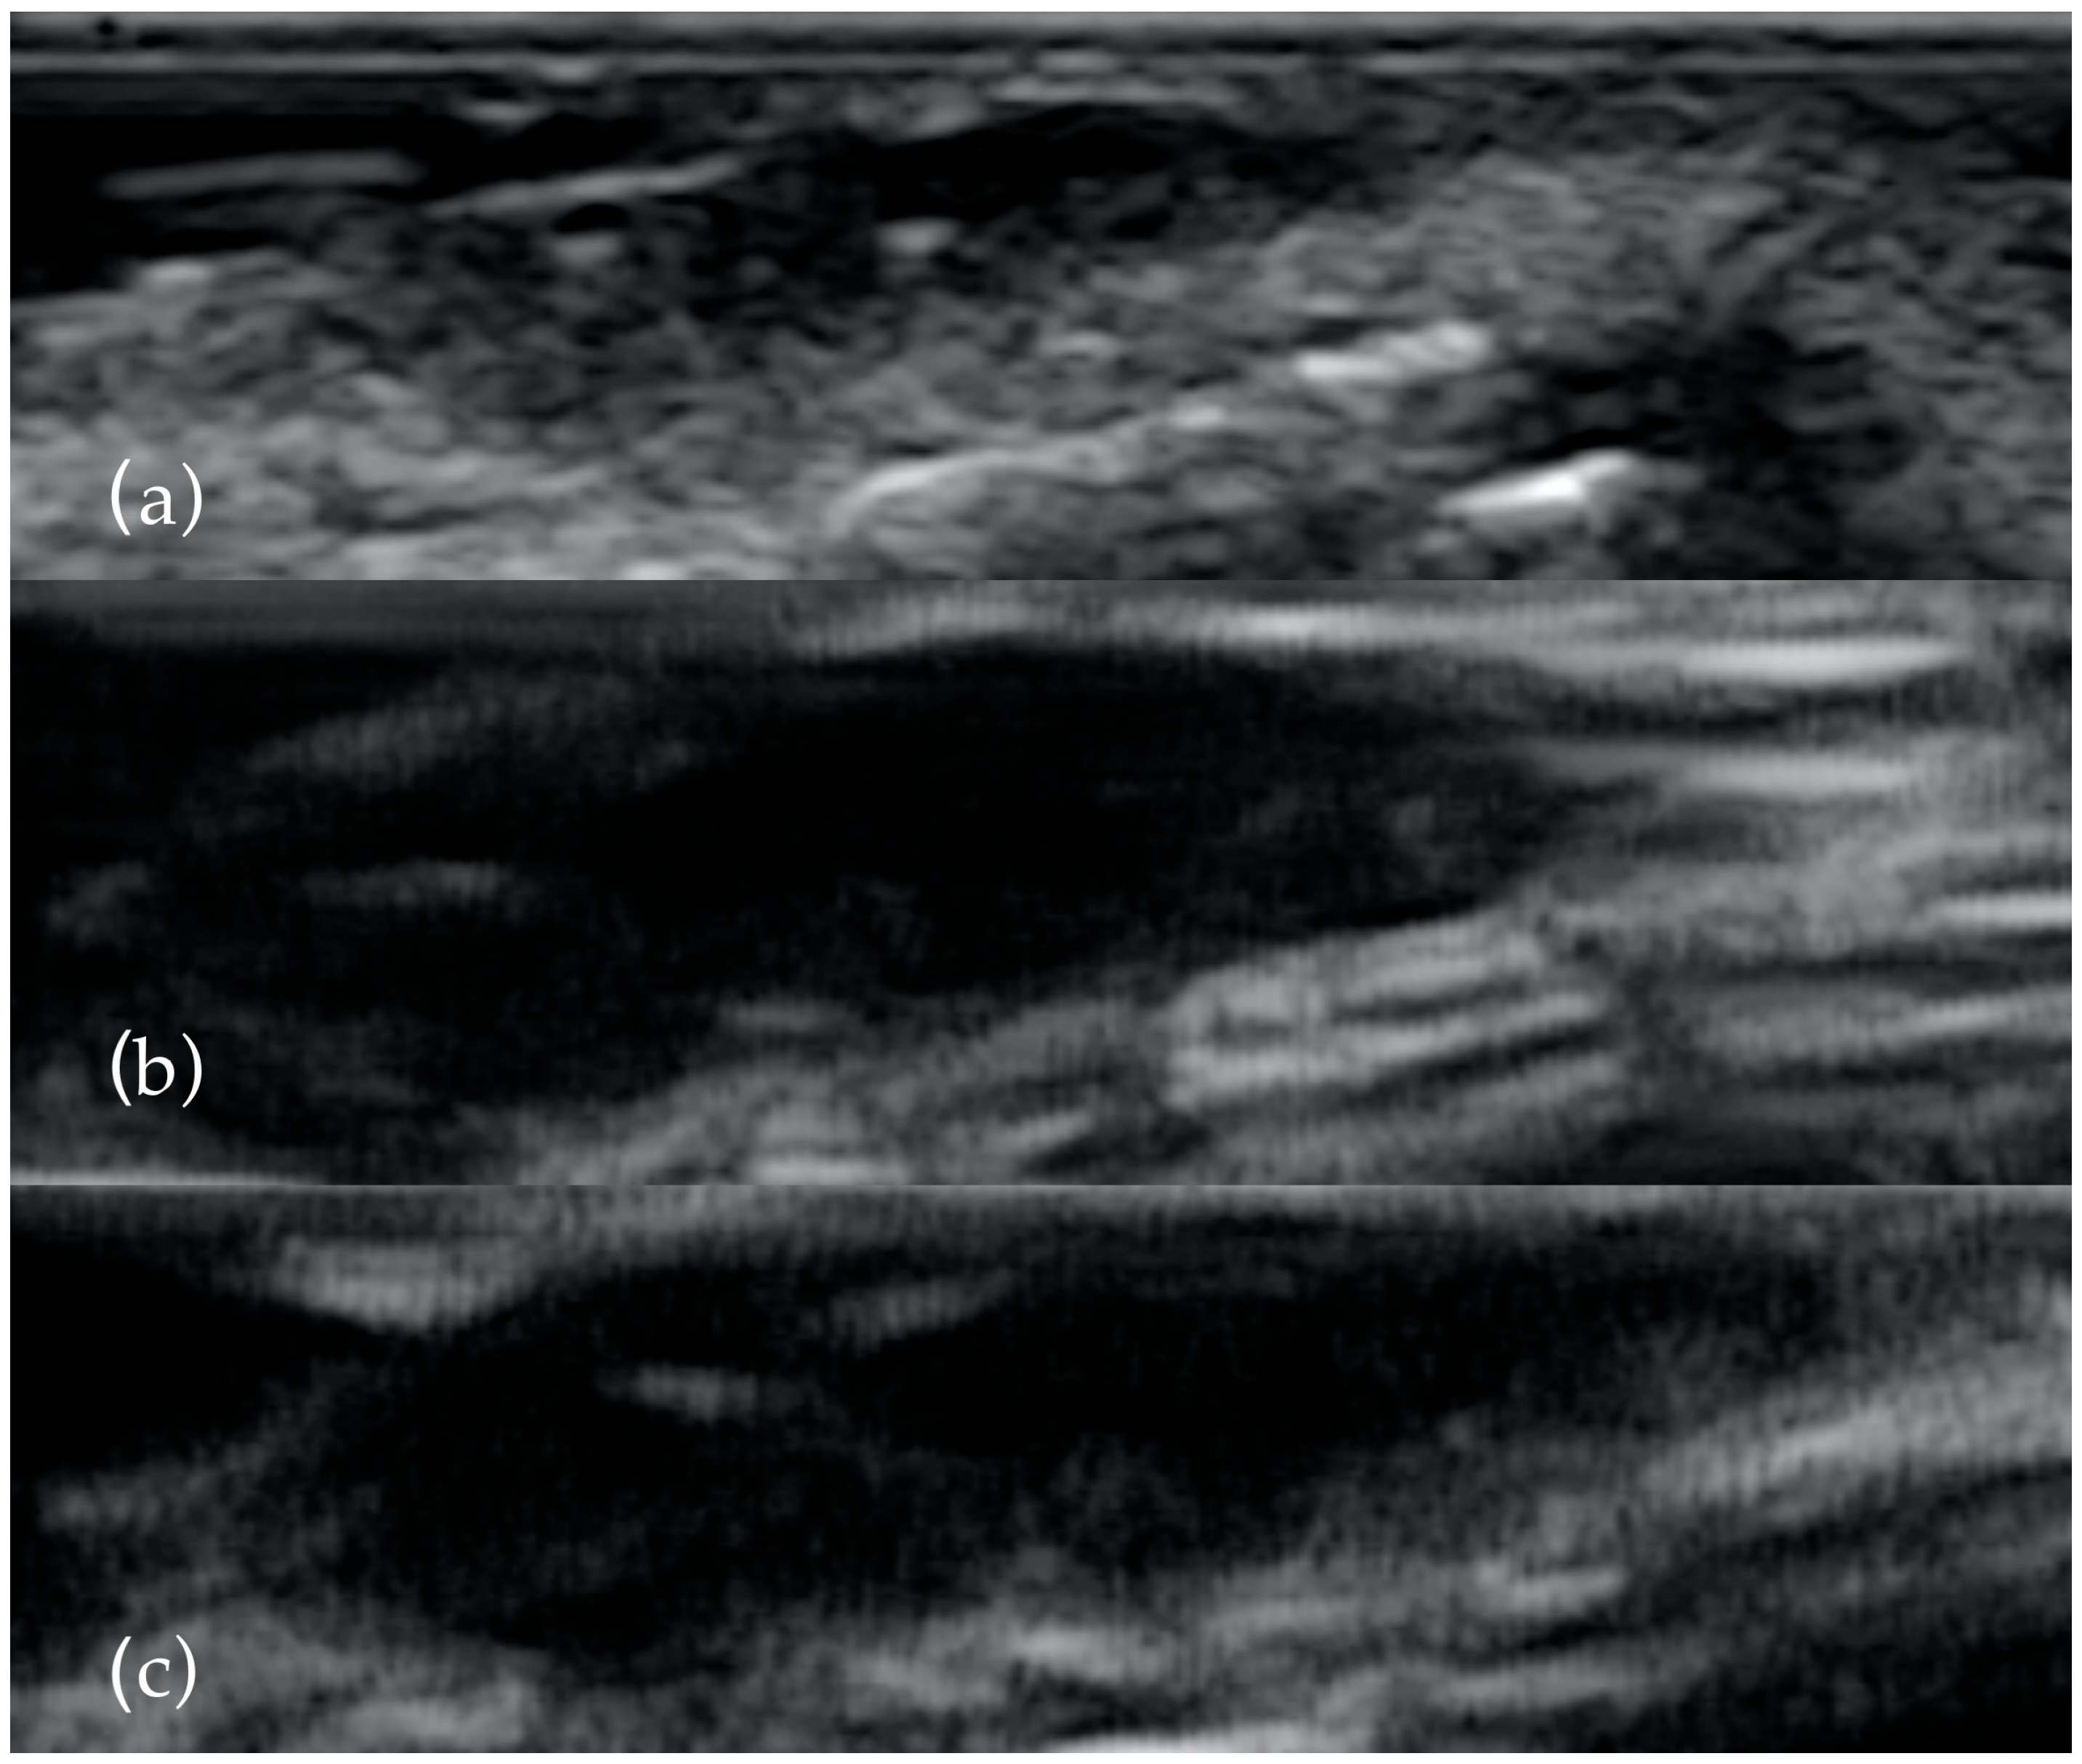

Thirty-one patients with highly suspicious malignant lesions of the head and neck skin were evaluated in the Oral and Maxillo-facial Surgery Department and Imaging Department in Cluj Napoca, Romania. All patients were informed of the study and agreed to participate. The Ethical Committee of the Emergency County Hospital Cluj-Napoca, Romania (39109/A/0001/UK/R Reg. n. 362/08.01.2020) and the Iuliu Hatieganu University of Medicine and Pharmacy Cluj-Napoca, Romania (433/11.10.2019) approved the study. After clinical examination, the patients were investigated by ultrasonography with high frequency transducers. All tumors were measured with three transducers: 13 MHz, 20 MHz and 40 MHz (Figure 1). Doppler examination and elastography were also used. The length, width, diameter, thickness, the presence of necrosis, status of regional lymph nodes, the presence of hyperechoic spots, strain ratio and vascularization were all recorded. All patients were treated by surgical resection of the tumor and reconstruction of the defect (Figure 2). Immediately after surgical resection, all tumors were placed with the epidermis facing up on sterile gauze and fixed with small-gauge needles. A layer of US gel was applied. The tumors were measured again after the same protocol. Doppler and elastography techniques were not performed. The resection margins were evaluated by all three types of transducers in order to detect malignant involvement of the resection margins or to measure the closest margin to the tumor. The results were compared with the histopathological report.

Figure 1.

The same BCC examined with 13 MHz (a), 20 MHz (b) and 40 MHz (c). As the frequency increases, the presence of the two hyperechoyc spots is clearer.

The US transducers frequency used in other studies varies between 5–18 MHz. We used three different transducers in order to obtain the closest measurement and to see the advantages and disadvantages of each one. The 13 MHz transducers offered a big picture of the tumor but the level of details, in the form of the presence of the hyperechoic spots, is reduced. We recommend this transducer for evaluation of surgical margins or for large skin tumors. The 20 and 40 MHz transducers are better for viewing the particularities of malignant lesions and for an accurate measurement but in the case of large size lesions, assessing of all three dimensions of the tumor can be difficult. Increasing the resolution of transducers obtains better level of details but, unfortunately, the level of penetrance decreases [6].